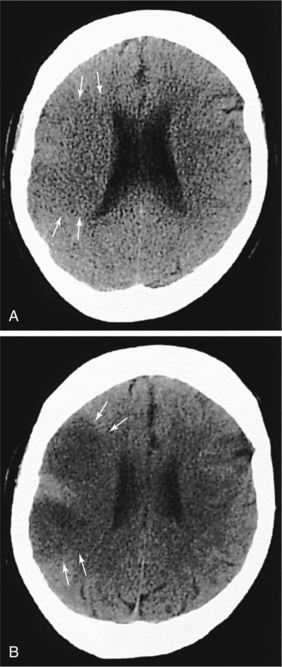

Neuroimaging of the brain has become a standard procedure in the diagnosis of stroke. Computed tomographic (CT) scan is the fastest, most convenient and widely available test to use for the diagnosis and early treatment of acute stroke. It can confirm the diagnosis and rule out other pathologies and extent of the lesion. Fig. 32-12 shows how an acute stroke looks on CT. However, CT scans may be normal in the acute stage of an embolic stroke. Bleeding into the brain tissue is seen acutely in a hemorrhagic stroke. Displacement of brain structures, such as the ventricles, by edema sometimes can be seen early in a large infarct. In ischemic stroke, CT scans reveal the area of decreased density and loss of grey/white matter differentiation resulting from edema. Cortical lesions appear wedge shaped and deeper lesions appear to be round or oval. Potential for hemorrhagic transformation of the ischemic infarct can be seen on CT.75 Lacunar infarcts are sometimes visible on CT scans as small, punched-out, hypodense areas. Images of lacunae and be seen in Fig. 32-13. Identification of the penumbra and infarct core on hyperacute noncontrast and perfusion CT may lead to potentially more aggressive treatments related to reperfusion and to arrest progression of stroke damage in the early part of the stroke.74 Fig. 32-14 demonstrates how the use of new imaging techniques may assist in this goal.

Figure 32-12 CT scan taken 2 hours, 50 minutes after large right middle cerebral artery occlusion. There are subtle, ultra-early ischemic changes, including loss of the grey-white interface (arrows) and subtle evidence of sulcal effacement. B, CT scan of same patient approximately 8 hours after symptom onset shows acute hypodensity (arrows) and more prominent sulcal effacement. (Reprinted from Marx JA: Rosen’s emergency medicine: concepts and clinical practice, ed 6, St Louis, 2006, Mosby.)